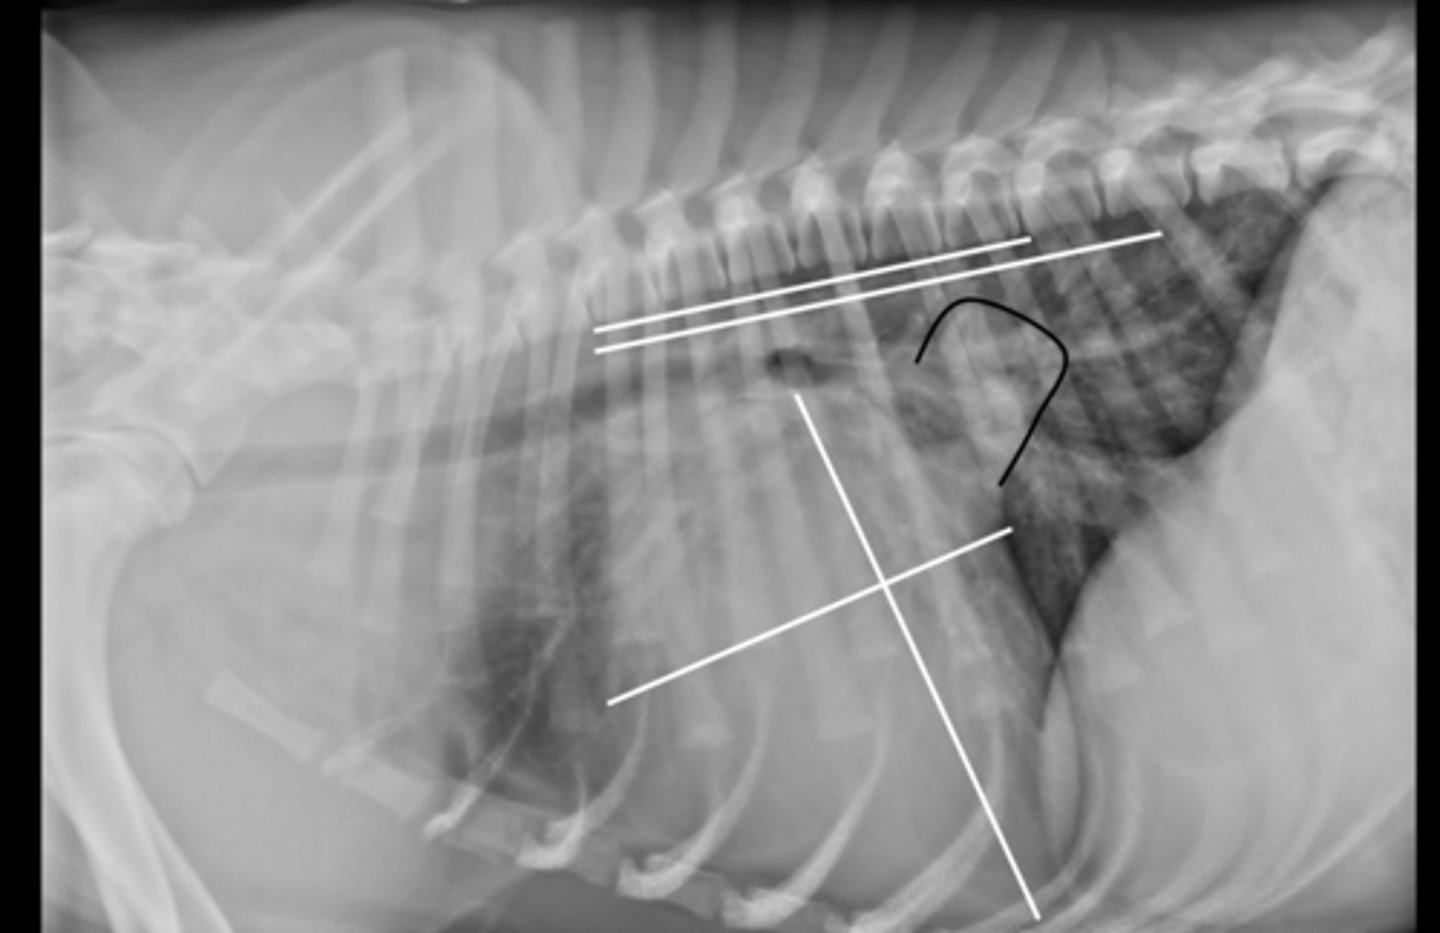

Heart - 13.5VHS

L atrial enlargement

Dilated pulmonary A. and V.

Given the radiograph which structures are enlarged?

DCM

-stage c

- Interstitial lung pattern suggest CHF

What is your dx?